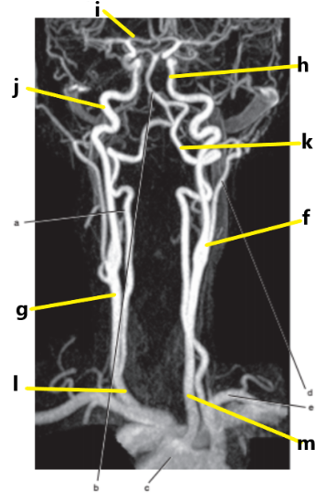

What is letter l ?

Common carotid

What is letter e ?

Subclavian artery

What is letter f ?

Common carotid artery

What is letter i ?

Anterior cerebral artery

What is letter m ?

What is letter j ?

Internal carotid artery

What is letter g ?

What is letter a ?

Vertebral artery

Aortic arch

What is letter b ?

External carotid artery

What is letter k ?

Basilar artery

Carotid sinus/bifurcation